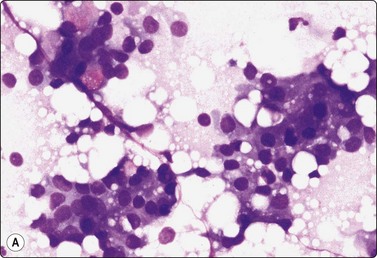

image image

Fig. 7.15 Regenerative epithelial atypia in mastitis

(A) Atypical, reactive/regenerating epithelial cells with a background of histiocytes, inflammatory cells and debris (MGG, HP); (B) Corresponding tissue section (H&E, IP).

Problems and differential diagnosis

Regenerative atypia of duct epithelium in an area of mastitis can look worrying and suspicious (Figs 7.15A and 7.17). In addition, the nuclei of reactive histiocytes may appear large and atypical, particularly in air-dried smears. False-positive diagnoses in cases of chronic mastitis and organizing fat necrosis have been reported. However, large numbers of both acute and chronic inflammatory cells are rarely seen in carcinoma. In medullary carcinoma with lymphocytic infiltration and in comedocarcinoma, in which lymphocytes and histiocytes are mixed with the carcinoma cells, the latter dominate and nuclear morphology is obviously malignant. The presence of necrotic cell debris should evoke a suspicion of malignancy.